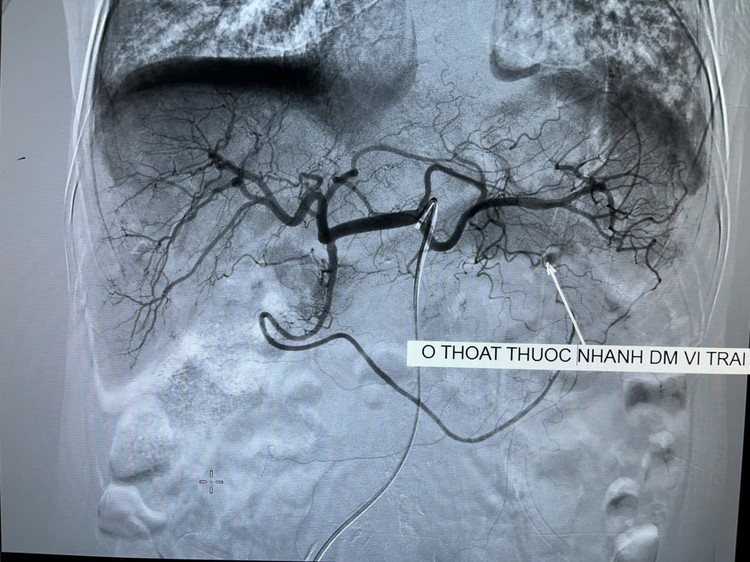

Qua chụp CT tiêm thuốc cản quang và chụp mạch trên máy DSA, thấy được vị trí chảy máu dạ dày tương đối lớn. Các bác sĩ đã tiến hành nút tắc toàn bộ nhánh động mạch chảy máu. Sau can thiệp, chụp kiểm tra lại, hệ thống động mạch không còn điểm chảy máu nào khác trong ống tiêu hóa.

Kỹ thuật nút mạch cầm máu chảy máu tiêu hóa cao cũng như xuất huyết các tạng trong ổ bụng là kỹ thuật tiên tiến nhất, can thiệp tối thiểu và đạt hiệu quả tối đa.